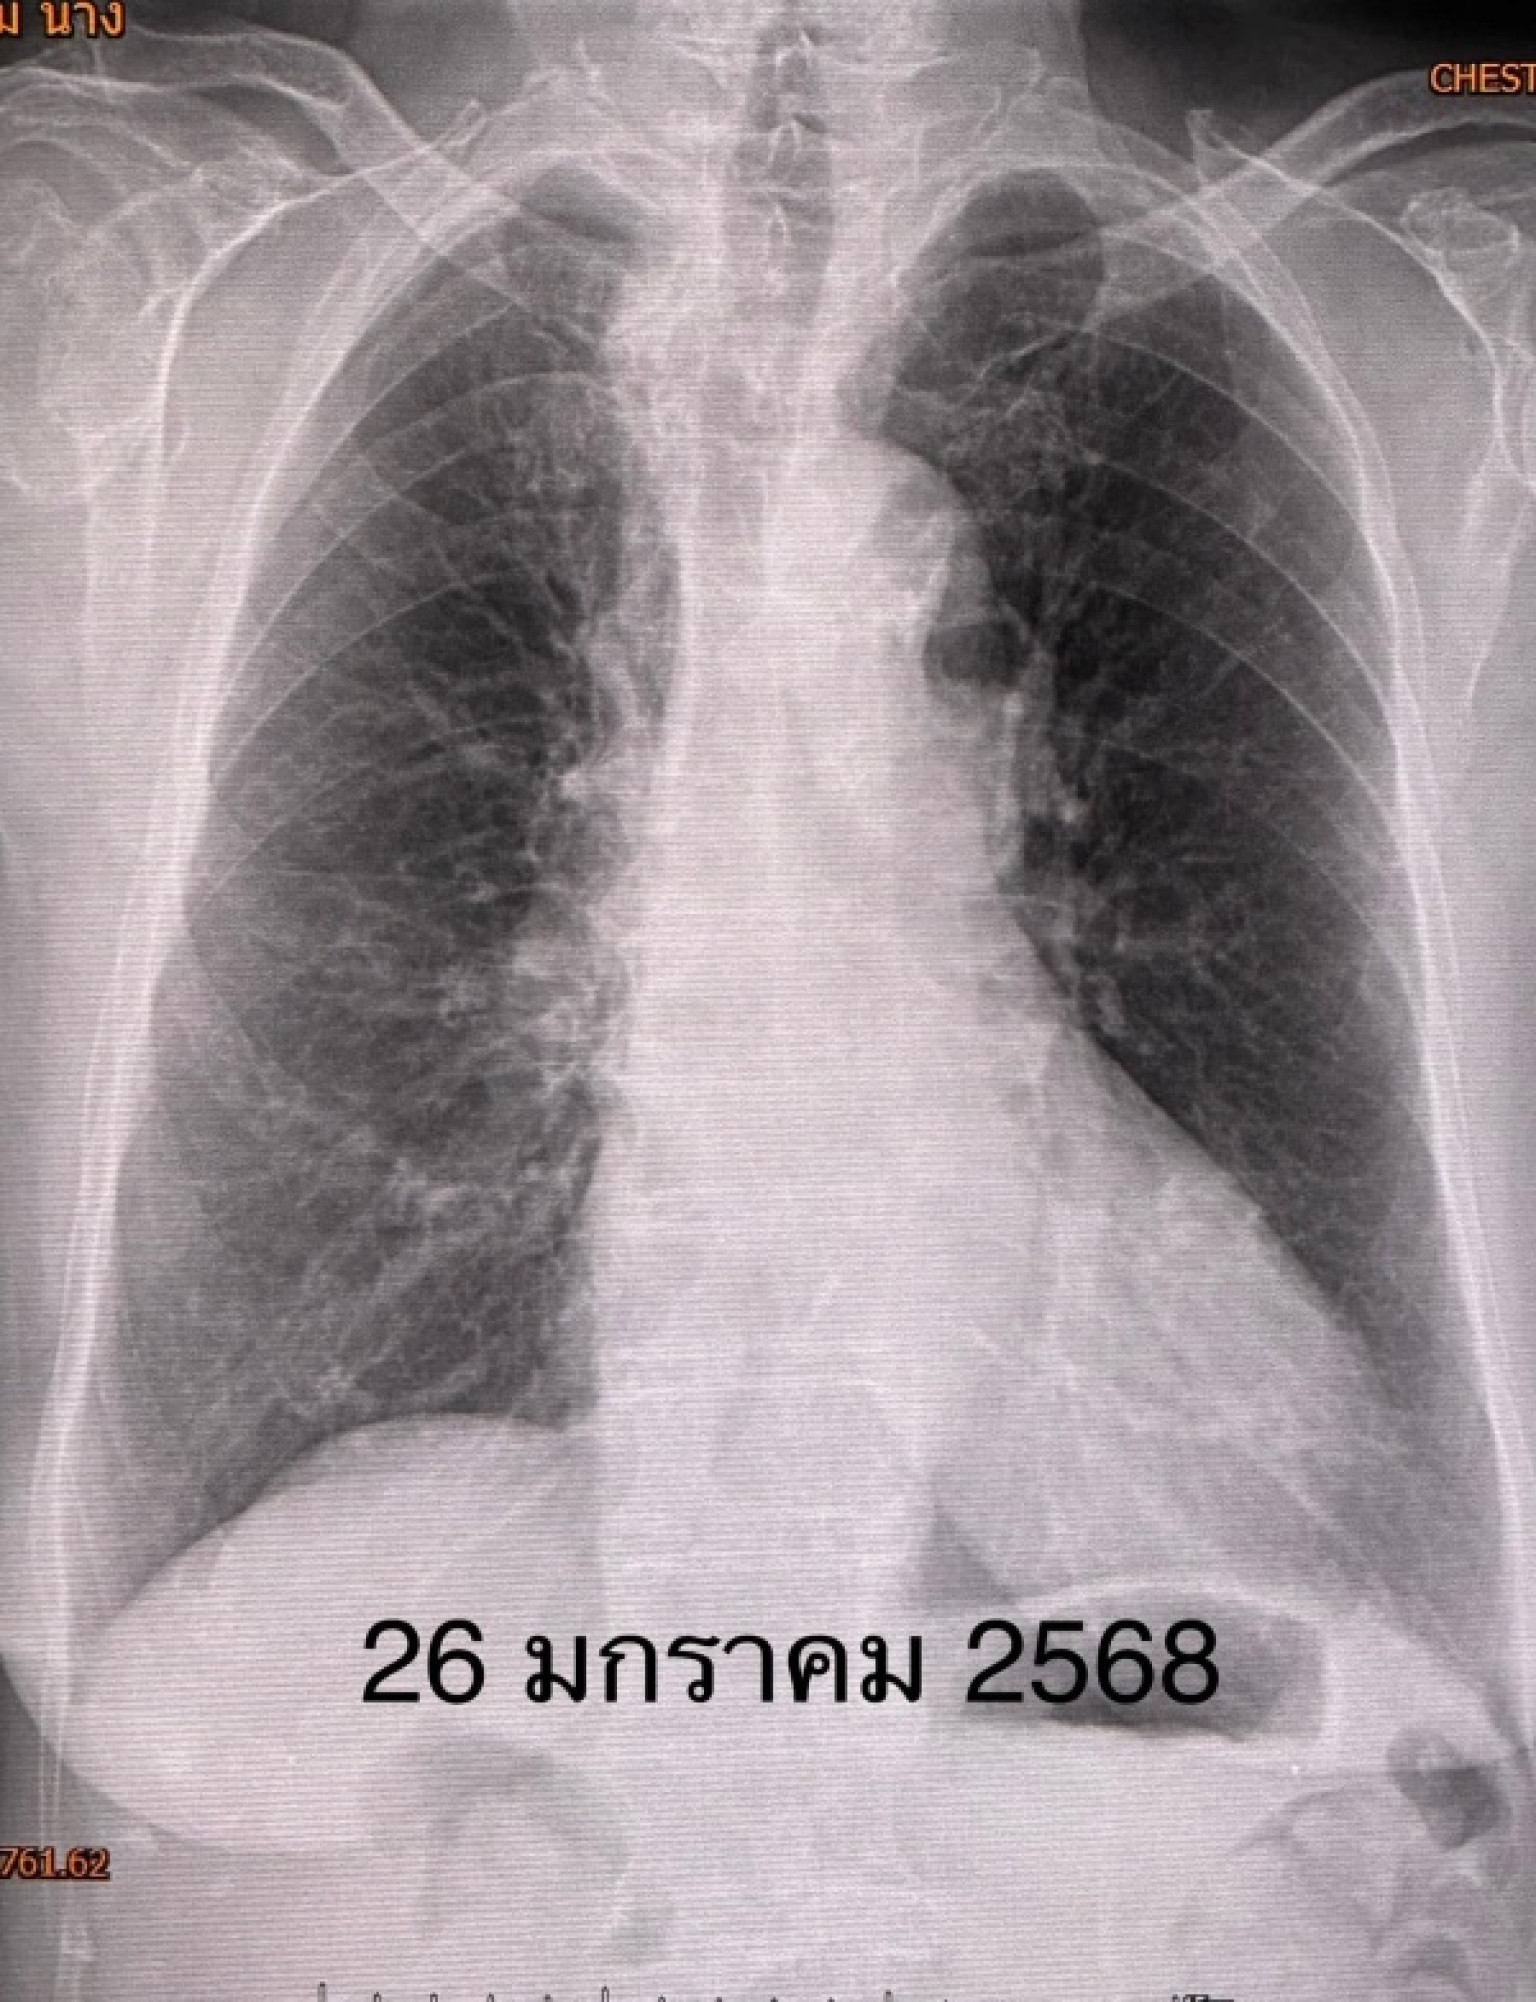

คนไข้ดีขึ้น ไม่ไอ ไม่เหนื่อย ระดับออกซิเจนปกติ ไม่ต้องใช้ออกซิเจน วันที่ 26 มกราคมเอกซเรย์ปอดกลับมาเป็นปกติ (ดูรูป)